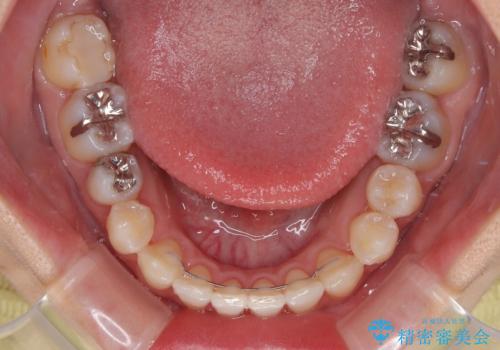

下顎歯列の叢生は軽度であることと、口元の突出感が全くなかったことから、八重歯解消のために上顎左右第一小臼歯を抜歯し、ワイヤー装置にて矯正治療を行うこととしました。

八重歯をスムーズに解消するために、補助装置を用いることで速やかに歯列を整えることができました。